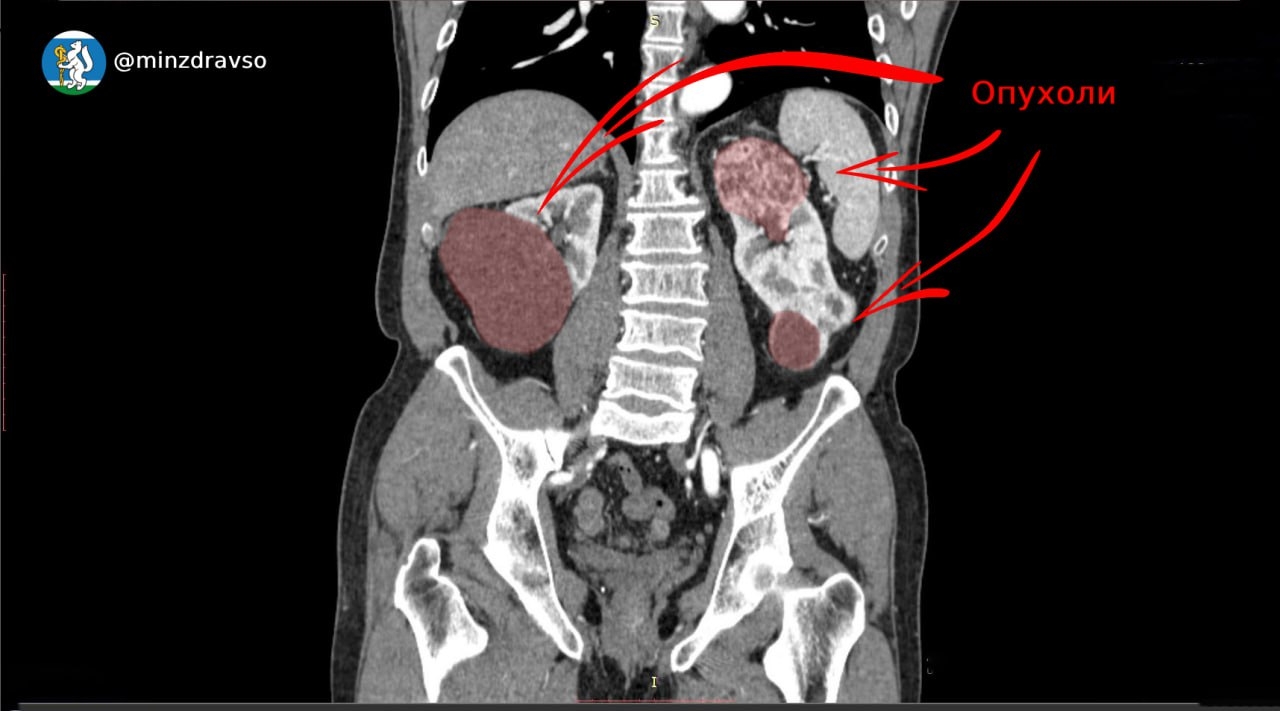

Патологию у мужчины обнаружили во время планового медосмотра. При углубленном обследовании выяснилось, что правая почка более чем наполовину поражена опухолью диаметром свыше 6 см. Орган пришлось удалить.

Но и левая почка оказалась поражена двумя крупными новообразованиями. Чтобы сохранить ее функцию, онкоурологи провели сложнейшую операцию по удалению опухолей общим размером 12 см, сохранив 70% здоровой ткани.

Операция прошла успешно, с минимальным временем ишемии — всего 12 минут. Сейчас пациент продолжает восстановление.